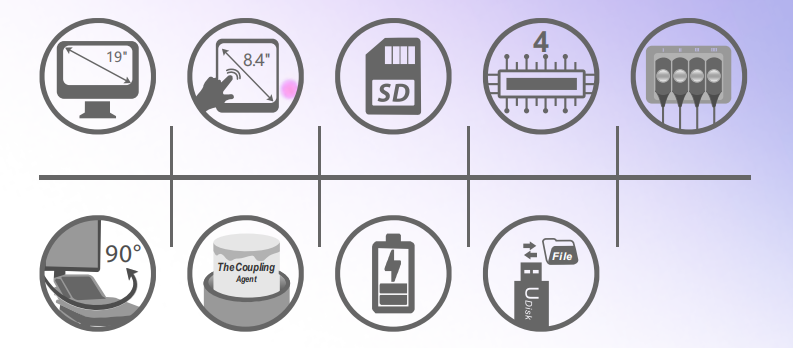

MSLTU02 is an updated design of the medical ultrasound model in terms of function and appearance. It is ideal for abdominal, ob/gyn, small parts, urology, cardiology and other applications. In addition, it offers a variety of image transfer and storage solutions, such as a USB port for transferring and saving images.

1. High frequency beamformer ensures optimal

2. Image resolution

3. 15-inch professional display, no flicker, reducing operator eye fatigue

4. Wide application: obstetrics. Gynecology, Urology, Cardiology, Small Parts

5. The measurement report is automatically generated

6. High-density probe and wider frequency band optimize image quality, the highest frequency can reach 7MHz